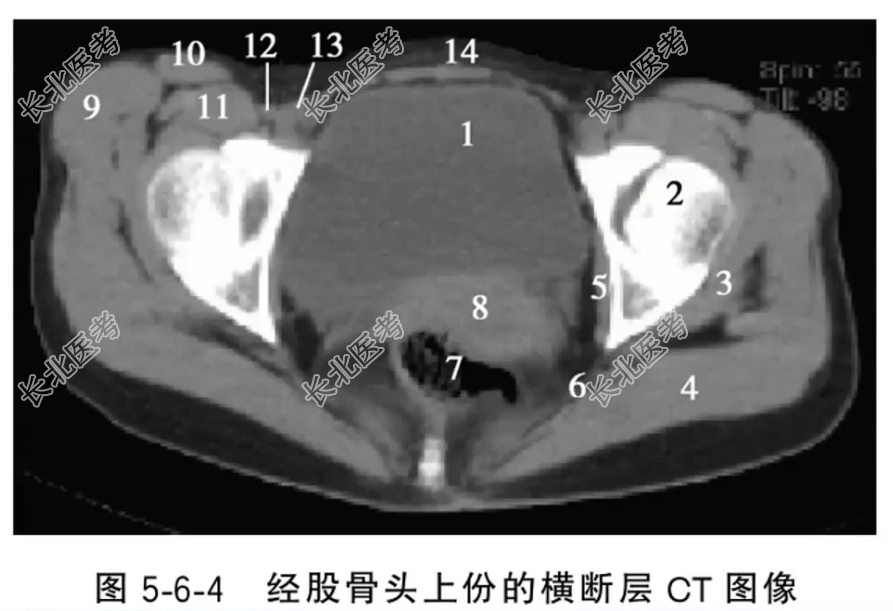

- 单项选择题经股骨头上份的横断层CT图像中,标记为5的结构是什么

A、上孖肌

B、闭孔内肌

C、臀大肌

D、髂腰肌

E、缝匠肌